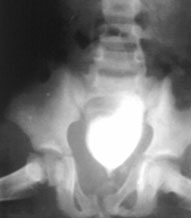

(1)骨盆后前位X线片:X线平片检查一般可明确骨折部位骨折类型及其移位情况,亦常能提示可能发生鵻的并发症。全骨盆后前位X线片可显示骨盆全貌对疑有骨盆骨折者应常规拍摄全骨盆后前位X线片以防漏诊对骨盆后前位X线片上显示有骨盆环骨折者,为明确了解骨折移位情况还应再摄骨盆入口位和出口位片。(2)骨盆入口位片:患者仰卧,X射线从颅侧投向尾侧,与片盒成60°倾斜摄片本位片可显示耻骨段骨折移位;骨盆向内、向外旋转和向内移位的程度;骶髂关节向后移位及骶骨骨折是否侵犯椎管;同样可显示坐骨棘撕脱骨折。

CT检查对骨盆骨折虽不属常规但它可在多个平面上清晰显示骶髂关节及其周围骨折或髋臼骨折的移位情况,因此凡涉及后环和髋臼的骨折应行CT检查骨盆三维重建CT或螺旋CT检查更能从整体显示骨盆损伤后的全貌,对指导骨折治疗颇有助益但应铭记对血流动力学鵻不稳定和多发伤患者,后前位全骨盆X线片是最基本和最重要鵻的放射学检查不要在拍摄特殊X线片上花费时间,更为重要的是尽快复苏。

2. 尿道或膀胱损伤。对骨盆骨折的病人应经常考虑下尿路损伤的可能性,尿道损伤远较膀胱损伤为多见。患者可出现排尿困难、尿道口溢血现象。双侧耻骨支骨折及耻骨联合分离时,尿道膜部损伤的发生率较高。